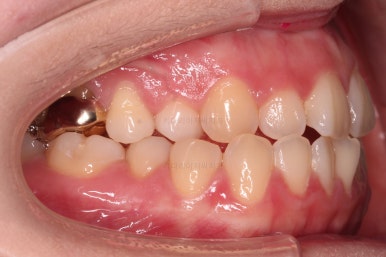

초진 시, 입안의 모습입니다.

아래 중앙선이 윗니의 정중선에 비해 우측으로 많이 쏠려있고요.

전반적으로 아래 치열이 우측으로 가 있어서 특히 송곳니 부분에서의 반대교합이 두드러졌어요.

(아래 송곳니가 위 송곳니보다 밖에 나와있는 상태)